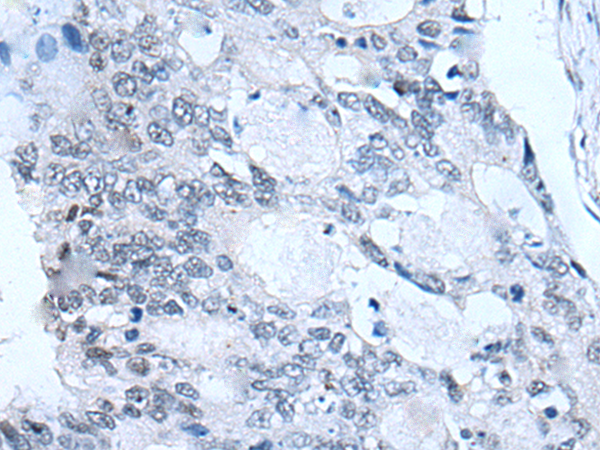

The image is immunohistochemistry of paraffin-embedded Human colorectal cancer tissue using P12730(FSHB Antibody) at dilution 1/30. (Original magnification: ×200) |